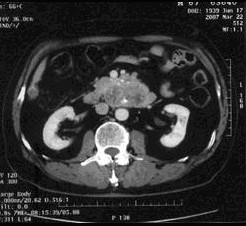

病例1 男,68歲,2006年12月14日,CT掃描發(fā)現(xiàn)胰頭占位性病變,6.0×4.7cm2,腹膜后淋巴結(jié)轉(zhuǎn)移,伴肝內(nèi)多發(fā)轉(zhuǎn)移灶。艾恒+希羅達(dá)化療3療程無效(圖1)。2007年4月5日,開始接受今又生治療,胰腺腫瘤內(nèi)注射今又生1×…